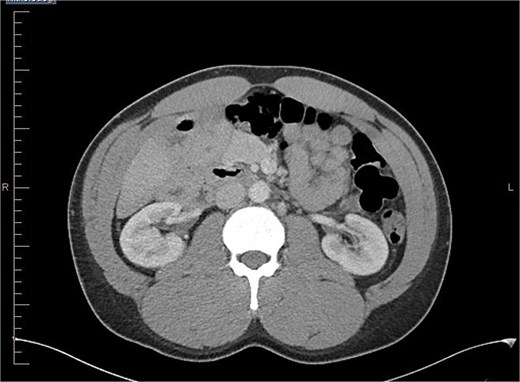

Axial view of abdominal CT scan with contrast showing the reversal of SMA and SMV.

The gold standard for diagnosing malrotation is an upper gastrointestinal (GI) series or a CT scan with oral and intravenous (IV) contrast. In adults, CT is preferred. Characteristic imaging findings include the ‘whirlpool’ sign (Fig. 3a and b), the superior mesenteric vein (SMV) rotation sign, where the SMV lies anterior to the superior mesenteric artery (SMA), as well as right-sided positioning of the bowel, duodenojejunal flexure, and cecum [8] (Fig. 4).